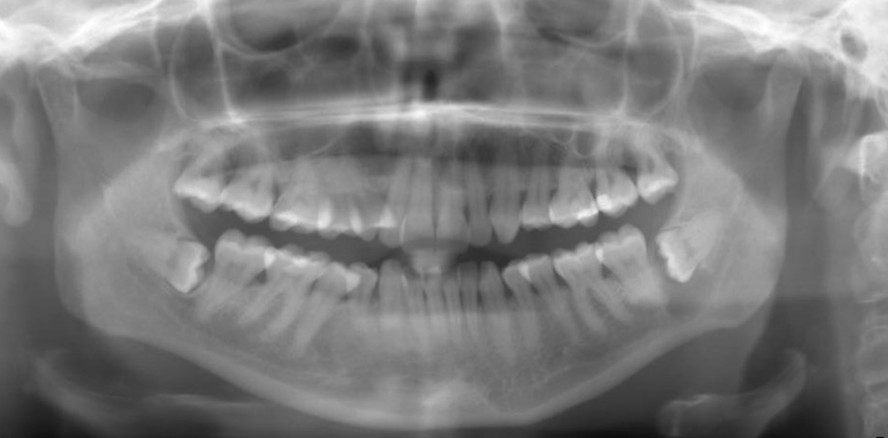

Dental-MRT: Detailliert, dreidimen­sional & ohne ionisierende Strahlung

Foto: Technischen Universität München

Die Anwendung der Dental-MRT bietet erhebliche Vorteile gegenüber herkömmlichen bildgebenden Verfahren. Mit der Dental-MRT können wir die Prozesse sichtbar machen, welche der DVT und der Röntgentechnik verborgen bleiben. Sie bietet so eine ideale Ergänzung zu den bereits etablierten Verfahren. Es werden zum Beispiel frühe entzündliche Veränderungen des zahntragenden Knochens und des Zahnhalteapparates, wie sie beispielsweise im Rahmen einer Parodontitis vorkommen, sichtbar, noch bevor es zum Knochensubstanzverlust gekommen ist. Mithilfe neuer MRT-Techniken ist es möglich, detaillierte, dreidimensionale Bilder von Kiefer- und Zahnstrukturen zu erhalten. Da die Technik frei ist von ionisierender Strahlung, können Krankheitsverläufe beobachtet aber auch Therapien überwacht werden. Insbesondere bei Kindern ist der Vorteil der Strahlenfreiheit maßgeblich.

Wir gewinnen durch Dental-MRT deutlich mehr Informationen über den Zustand und die Gesundheit der Patienten. Die Dental-MRT ermöglicht es uns, Nervenschädigungen direkt darzustellen. Durch eine frühzeitige Diagnose können die Weichen für eine gezielte, patientenspezifische Therapie gestellt werden. Im Speziellen nach Nervenschädigungen ist die Prognose stark von einer frühzeitigen Diagnostik und Therapie abhängig, damit der optimale Behandlungszeitraum nicht verpasst wird. Auch Traumapatienten profitieren von einer MRT-Diagnostik. So kann beispielsweise eine Pulpanekrose nach Frontzahntrauma detektiert werden. Auch nicht dislozierte Kieferfrakturen werden in der MRT durch ihre knöcherne Ödembildung sichtbar. Eine Besonderheit ist die Fähigkeit der Dental-MRT, aktiv entzündliche von narbig veränderten apikalen Osteolysen zu unterscheiden und somit im Bereich der Endodontie einen deutlichen Mehrwert zu bieten.